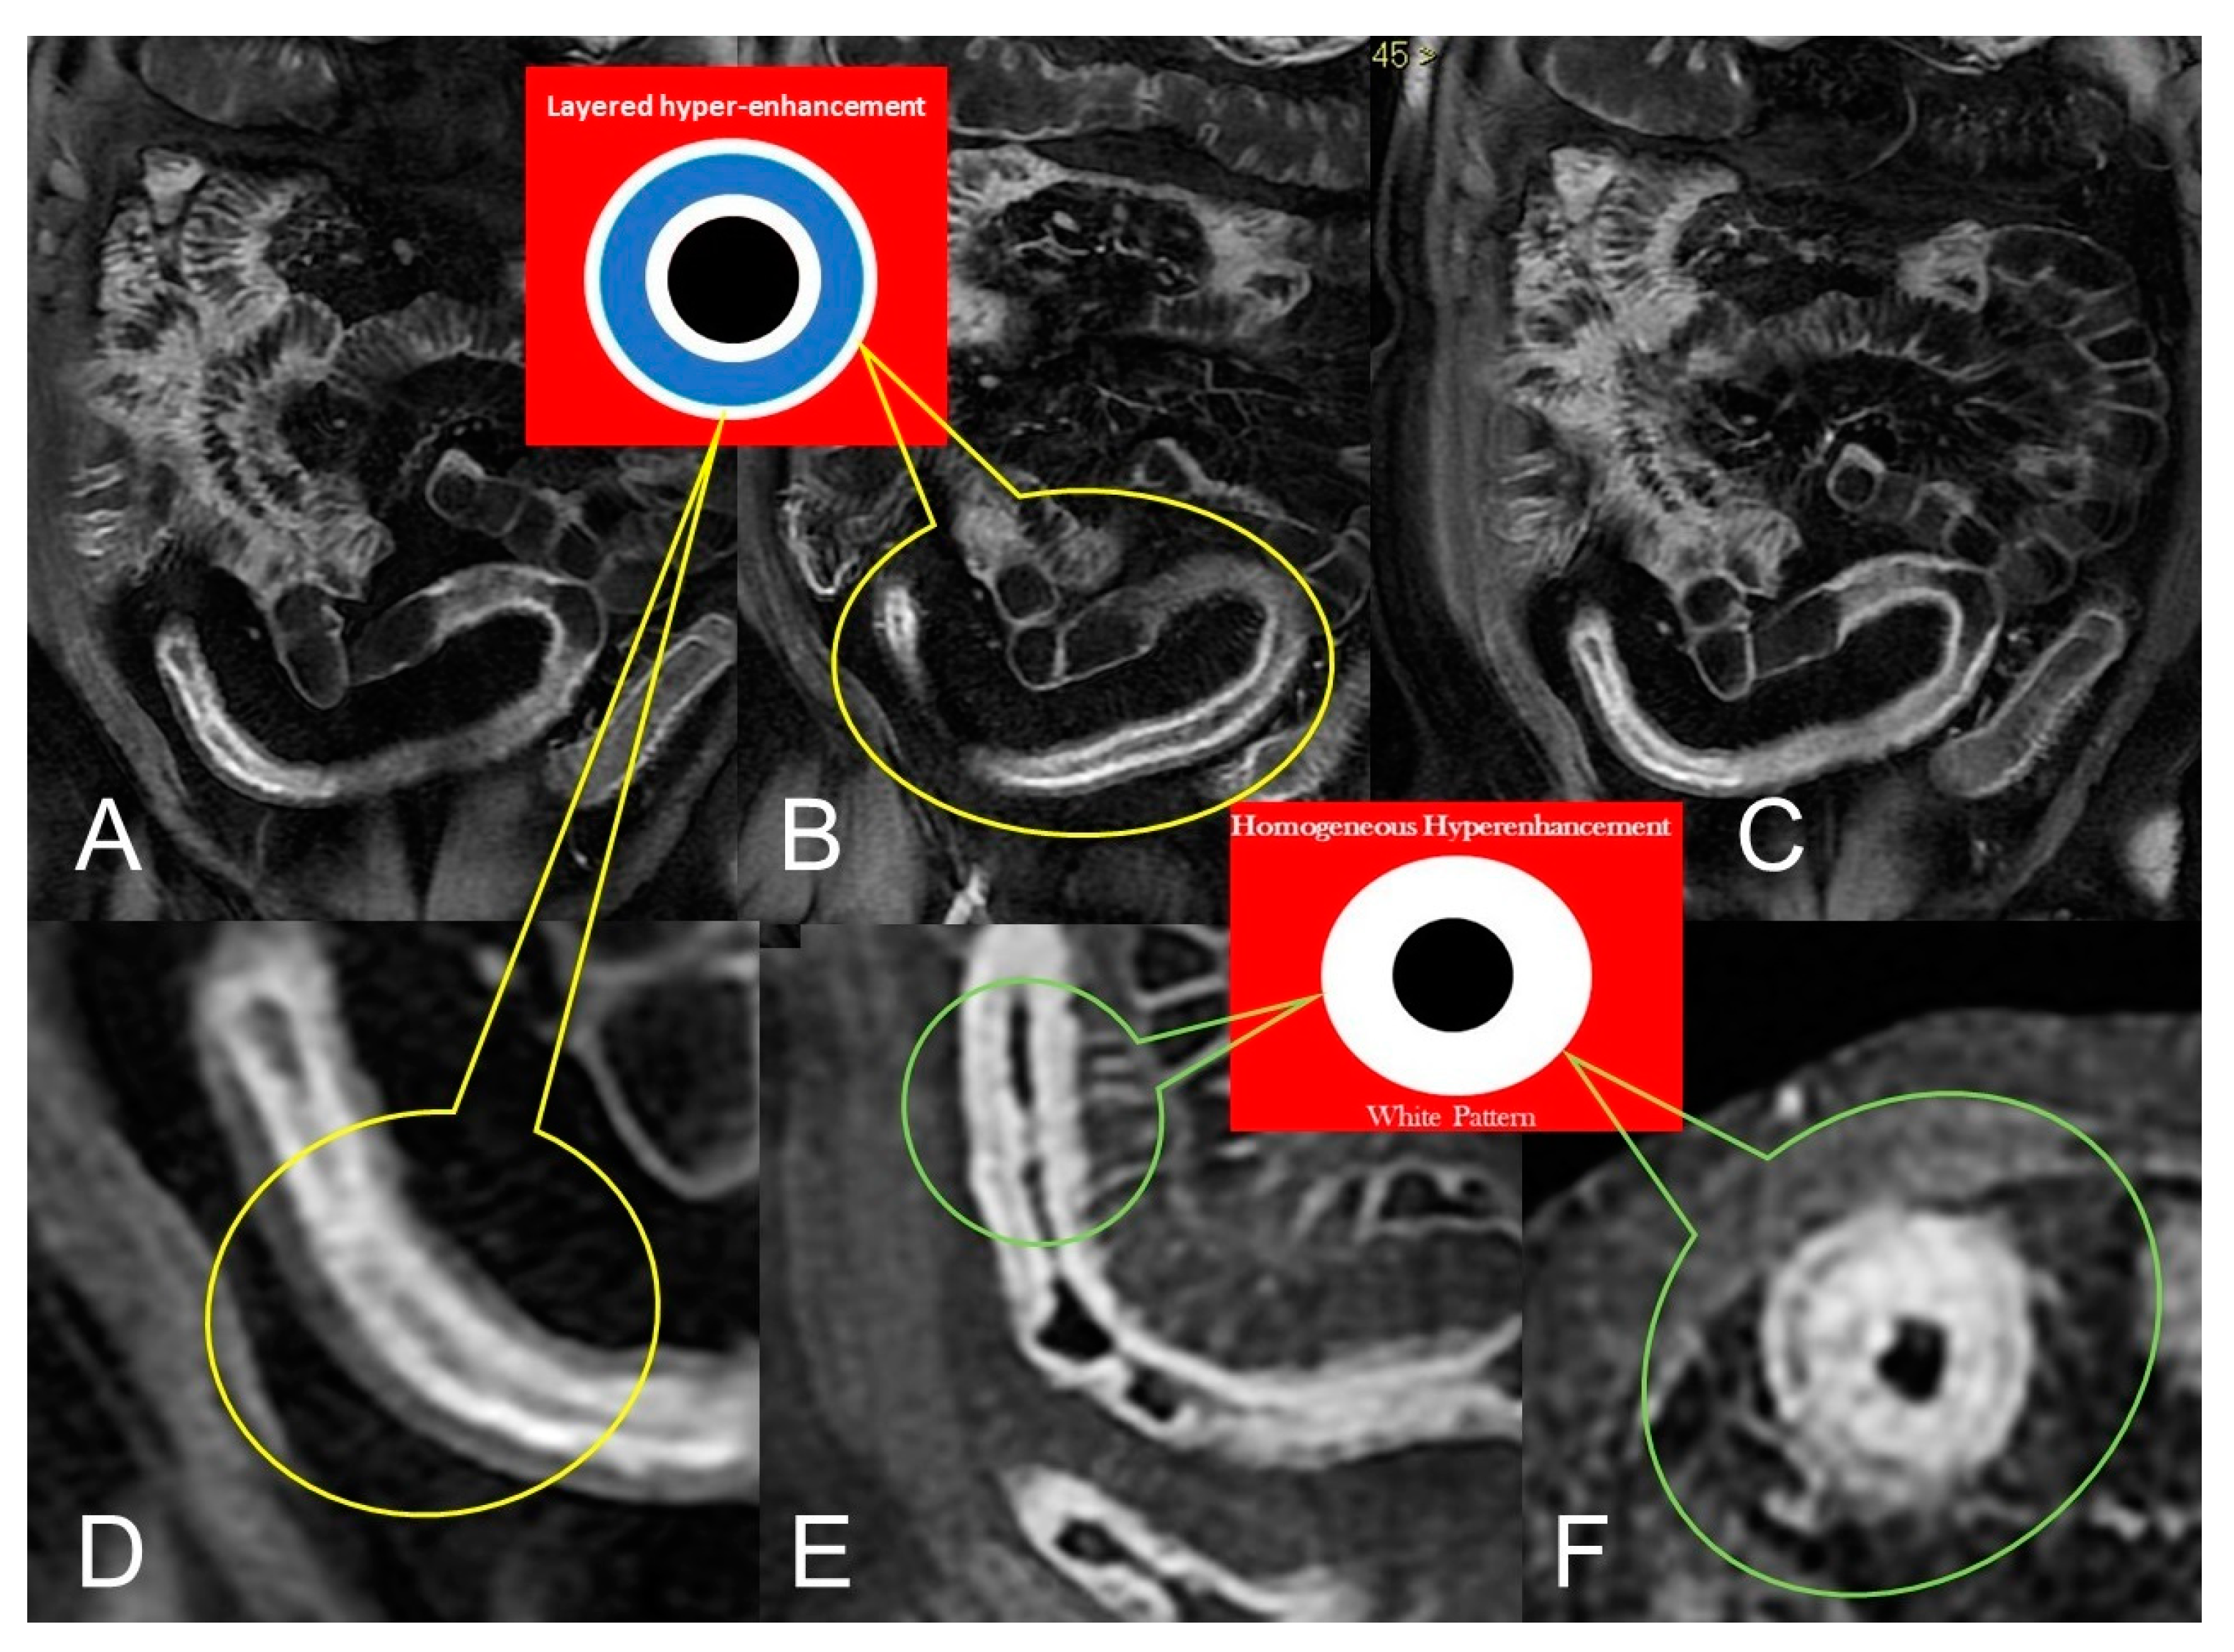

In CD, segmental bowel wall mural hyperenhancement represents the pathological tissue that at contrast-enhanced MRE is revealed as increased mural signal intensity in a small bowel’s segment compared with the normal adjacent intestinal tract [5]. Mural hyperenhancement can be asymmetric (in a small bowel loop, it could involve the mesenteric border more than the antimesenteric one), stratified (bilaminar or trilaminar inner-wall hyperenhancement or halo sign), or homogeneous (evenly distributed over the entire bowel wall). Submucosal edema, granulation tissue, intramural fat accumulation, fibrosis, or inflammatory infiltration may contribute to stratified enhancement (Figure 3 and Figure 4). Bowel wall enhancement evaluation is correctly depicted in the enteric phase (45–50 s after the intravenous contrast material injection begins) and/or in portal venous phase (60–70 s after the intravenous contrast material injection begins). Furthermore, we consider also that endoscopy and histopathological examination clearly show the absence of mucosa in the affected intestinal segments, so the term “mucosal hyperenhancement” is incorrect when the stratified enhancement pattern is expressed and should not be used. Finally, it must be underlined that the segmental bowel wall mural hyperenhancement is a sensitive but non-specific sign of CD, and therefore it must always be contextualized in the general framework of interpretation [6].

Figure 3.

Active inflammatory Crohn’s disease with layered hyper-enhancement pattern (A–D): the presence of active Crohn’s disease is indicated by small bowel wall thickening with layered hyperenhancement on coronal fat-suppressed contrast-Enhanced T1-Weighted MRE images. Active inflammatory Crohn’s disease with homogeneous enhancement pattern (E,F): the presence of active Crohn’s disease is indicated by small bowel wall thickening with homogeneous enhancement on coronal (E) and axial (F) fat-suppressed contrast-Enhanced T1-Weighted MRE images.

Figure 4.

Lack of layered or homogeneous enhancement can be related to fat ((B), axial FIESTA) image, or fibrosis parietal deposition, with poor enhancement and gray pattern on contrast-enhanced fat-suppressed T1-weighted image ((A), coronal image).